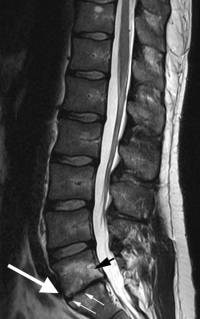

The MRI findings of isolated disc resorption (IDR) are classic. First, the disc will be very narrowed and have lost most of its original height. The disc space will appear black due to the loss of water from the nucleus and then loss of the nucleus itself.

The cortical endplates of the bone, which are normally uniform and regular, are found to be irregular with small endplate fractures. Some call these “moth-eaten” or “rat-bite” appearances.

The inside or internal body of the vertebra will be whitened along these fractured edges (noted on a T2 image in which water is white). This is due to fluid accumulation from the fractured trabecula, which seeps into this area.